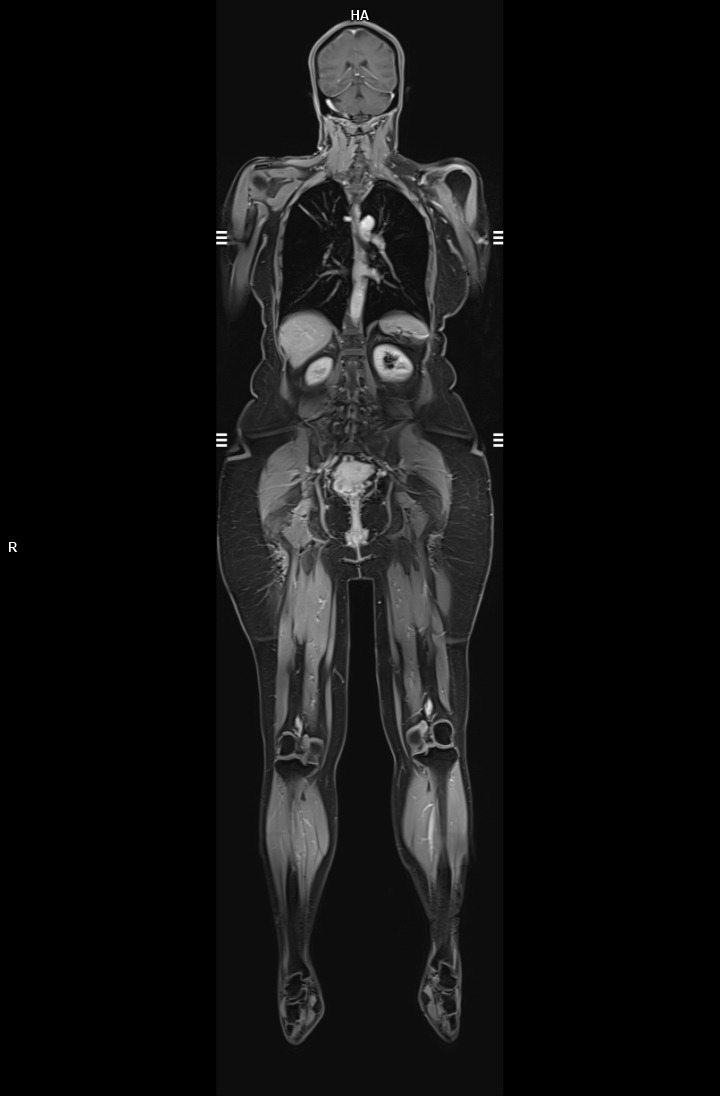

• Tüm Vücut MR

• 3 TESLA MR ÇEKİM GÖRÜNTÜLERİ

3 Tesla MR Çekim Görüntüleri

• 3 Tesla MR Çekim Görüntüleri